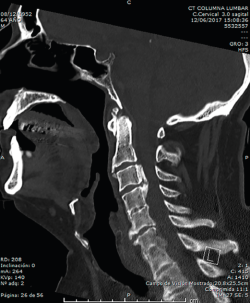

En la Figura 3 puede verse un corte sagital de la TAC cervical con sindesmofitosis también a este nivel, provocando un verdadero canal estrecho cervical en el raquis cervical alto.

Figura 3. Corte sagital de tomografía axial computarizada cervical.